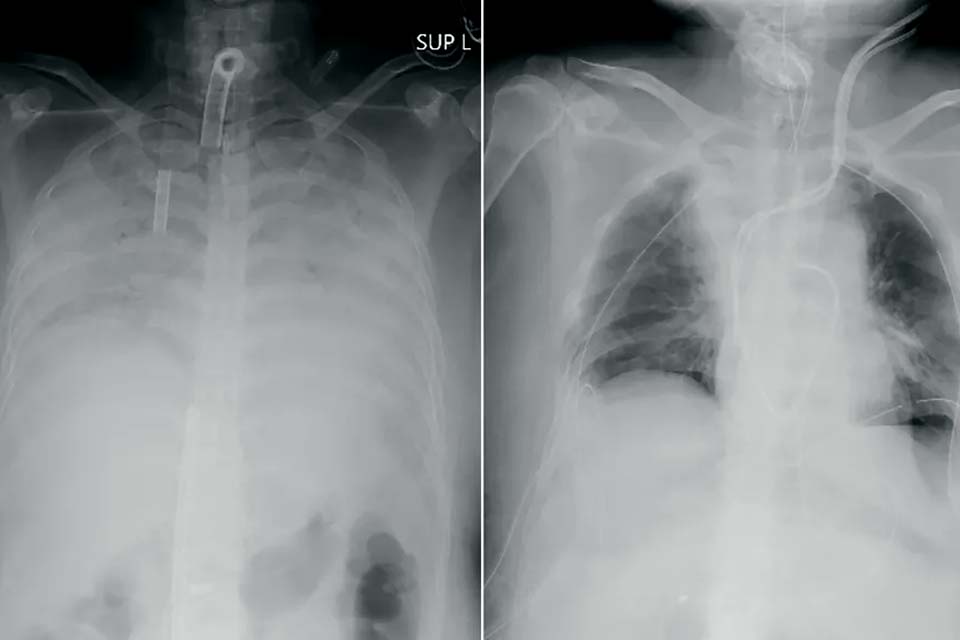

Japoneses anunciam o 1º transplante mundial de tecido pulmonar de doadores vivos para um paciente com grave lesão pulmonar causada pela Covid-19. Radiografias fornecidas em 9 de abril de 2021 pelo Hospital Universitário de Quioto mostram o tórax de um paciente antes da cirurgia (à esquerda) e depois — Foto: Hospital Universitário de Quioto via AP